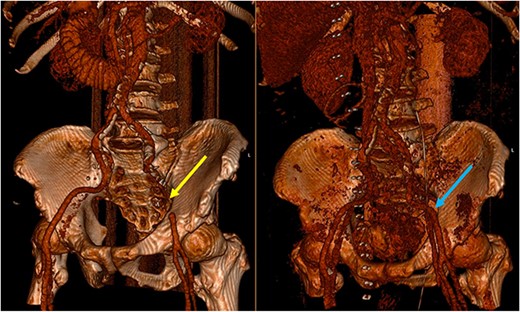

Three-dimensional reconstruction of the pre-operative (left) and post-operative (right) CT scan. The pre-operative CT demonstrates a segment of EIA that cannot be reconstructed due to the slow flow through the segment involved in the SBO (yellow arrow). The post-operative image demonstrates a patent EIA following vascular repair (blue arrow).

Pre-operative identification of internal hernias would allow for optimal management and planning, however diagnosis of intestinal herniation causing SBO on imaging can be challenging. CT features such as atypical bowel configuration, mesenteric abnormalities (including displacement, twisting or stretching of mesenteric vessels) and the position of surrounding viscera raise the index of suspicion of internal herniation [13]. In this case, retrospective review of the CT scan demonstrates the proximity and compression or partial occlusion of the segment of EIA within the closed-loop obstruction (Figs 3 and 4). This is concordant with our intra-operative findings of a narrow, non-pulsatile structure.